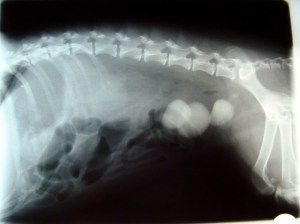

In some bladder infections, minerals in the urine crystallize and form bladder stones, which can be as small as grains of sand or larger than marbles or small rocks.

Your veterinarian may be able to feel stones by palpating the bladder (i.e., feeling it through the abdominal wall), but an x-ray or ultrasound is usually needed for a definite diagnosis.